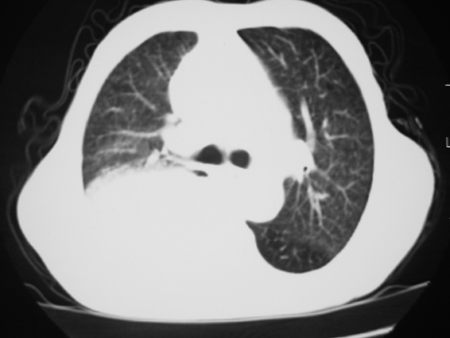

男77岁,胸痛就诊

右侧胸腔积液,部分包裹,右下肺膨胀不全,右下肺感染。

考虑右肺门占位并下叶不张 右胸包裹积液

右侧胸腔积液,部分包裹,右下肺膨胀不全

右肺中叶及下叶炎症并胸腔积液(部分包裹),建议抽液后复查ct除外占位。